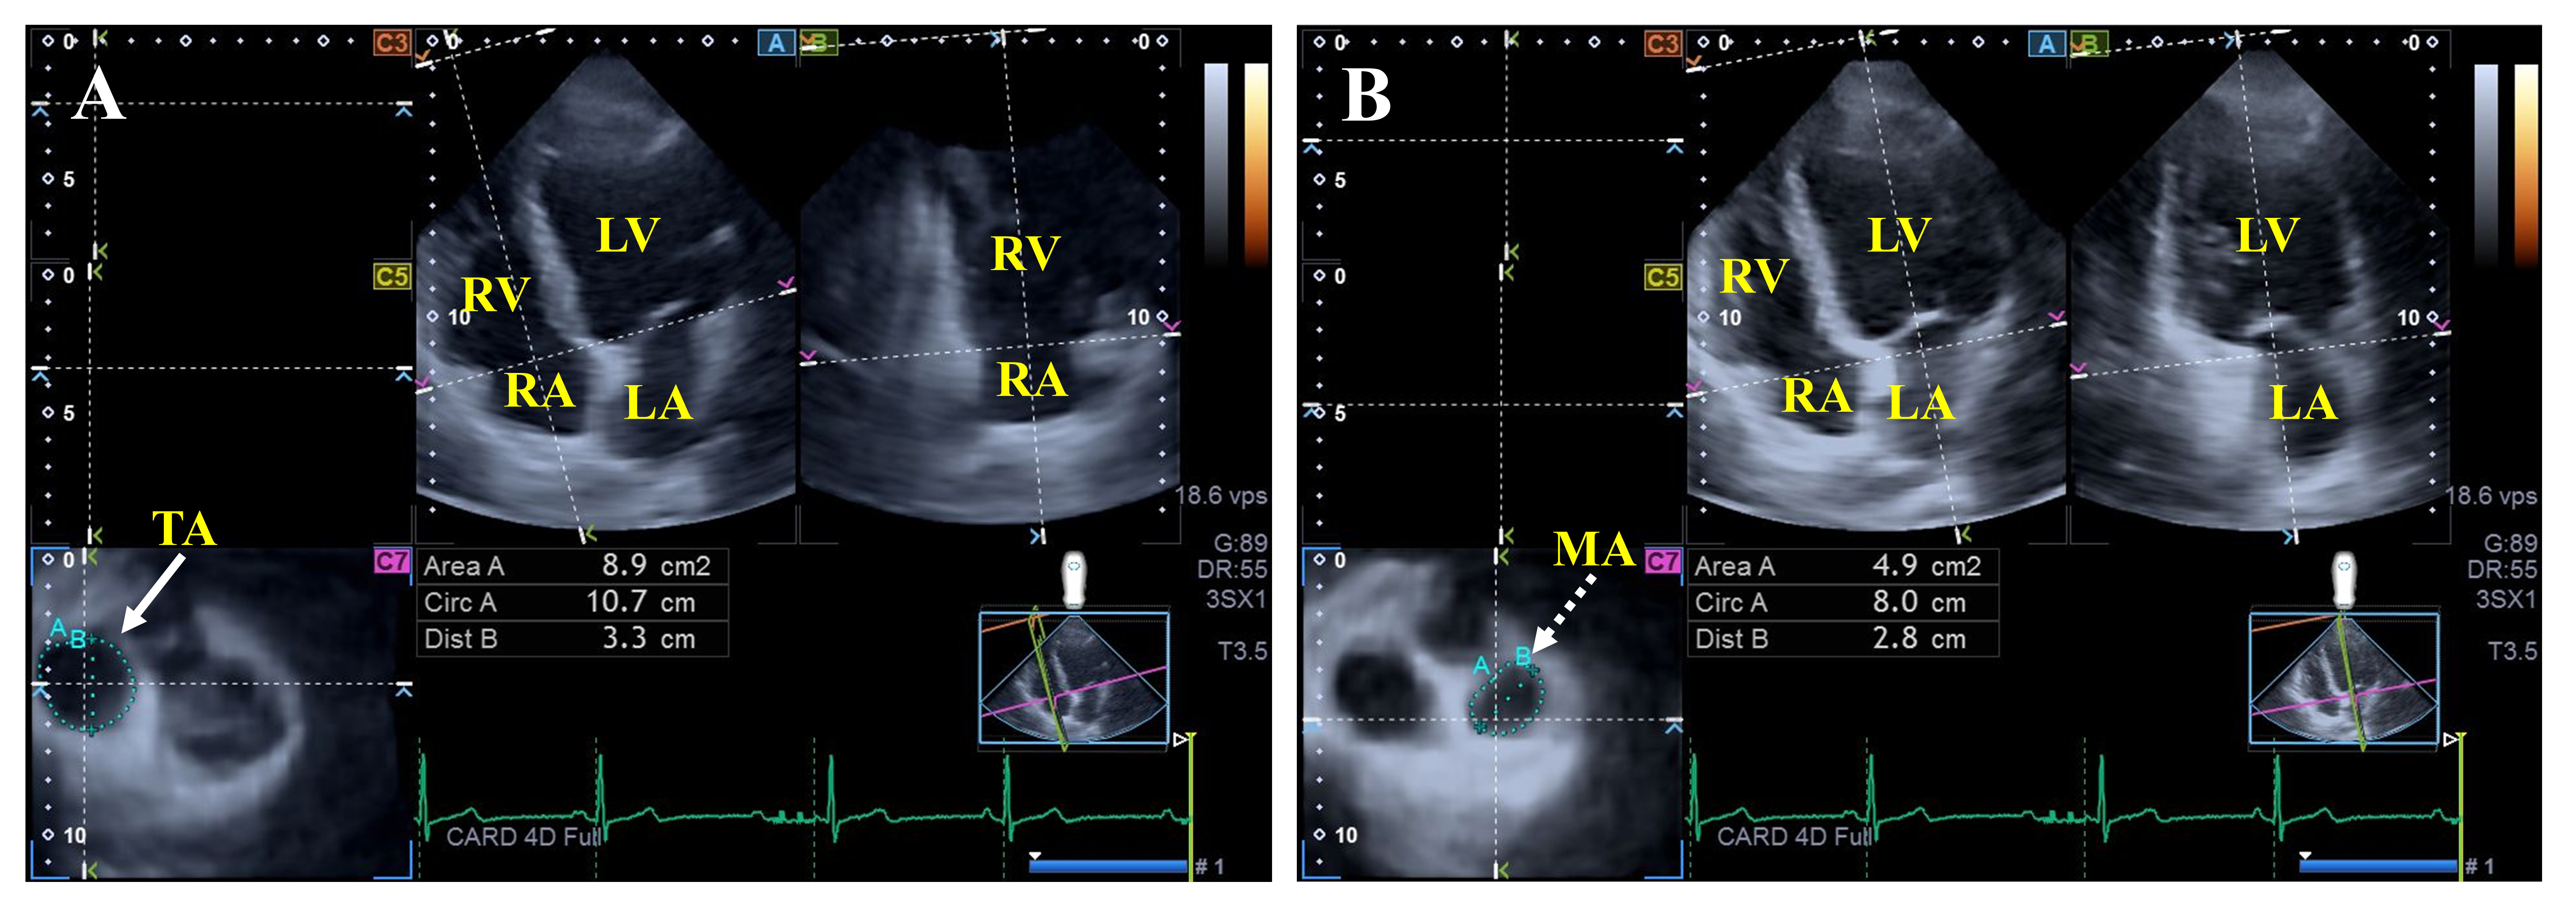

Fig. 3. Assessment of the tricuspid (A) and mitral annular (B) dimensions by three-dimensional speckle-tracking echocardiography. Abbreviations: LV, left ventricle; RA, right atrium; LA, left atrium; RV, right ventricle; Dist, diameter; Area, area; Circ, perimeter; TA, tricuspid annulus; MA, mitral annulus.

Findings from the MAGYAR-Path Study showed dilated MA diameters, areas, and perimeters measured both in end-systole and end-diastole in hemophilia patients, together with consequentially impaired MA fractional area change compared to healthy controls. Moreover, mitral valve abnormalities could not be detected in this study with hemophilia patients without any suspicion of cardiovascular pathologies [21].

Preserved end-systolic TA sizes and dilated end-diastolic TA perimeter, area, and diameter were present together with reduced TA fractional area change in hemophilia [21]. No data in the literature support that other TV abnormalities are more frequently associated with hemophilia patients compared to controls.